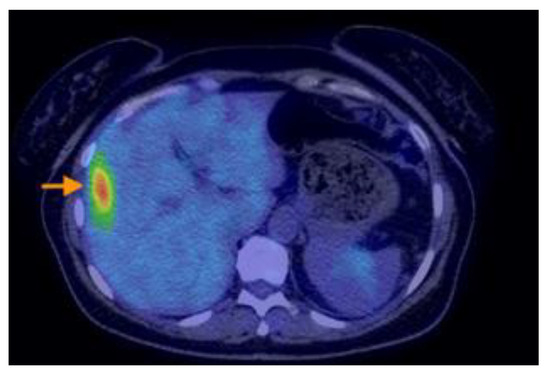

3.2.3. Imaging Findings, Diagnosis, and Differential Diagnosis